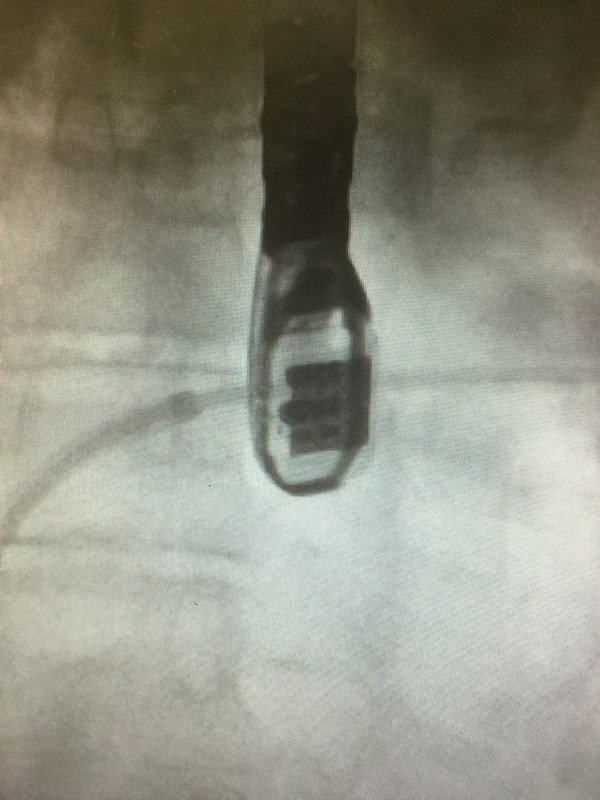

49 yaşında şeker,tansiyon ve ciddi kalp yetmezliği olan hastamız ciddi nefes darlığı,bacaklarında ödem ve karnında şişlik şikayetleriyle bize başvurdu. Yapılan eko muayenesi sonucu hastamızda ciddi kalp yetmezliği ve kalbin Mitral kapağında ciddi kaçak olduğunu tesbit ettik.Açık ameliyat şansının olmadiği söylenen hastamıza MitraClip(mitral kapağı mandallama) işlemini uygulamaya karar verdik. 5 gün önce işlem yaptığımız hastamız şikayetlerinde %90 azalmayla bu gün taburcu edildi..